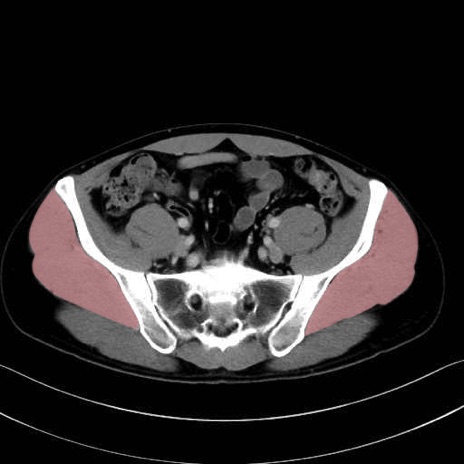

中殿筋 (Gluteus medius)